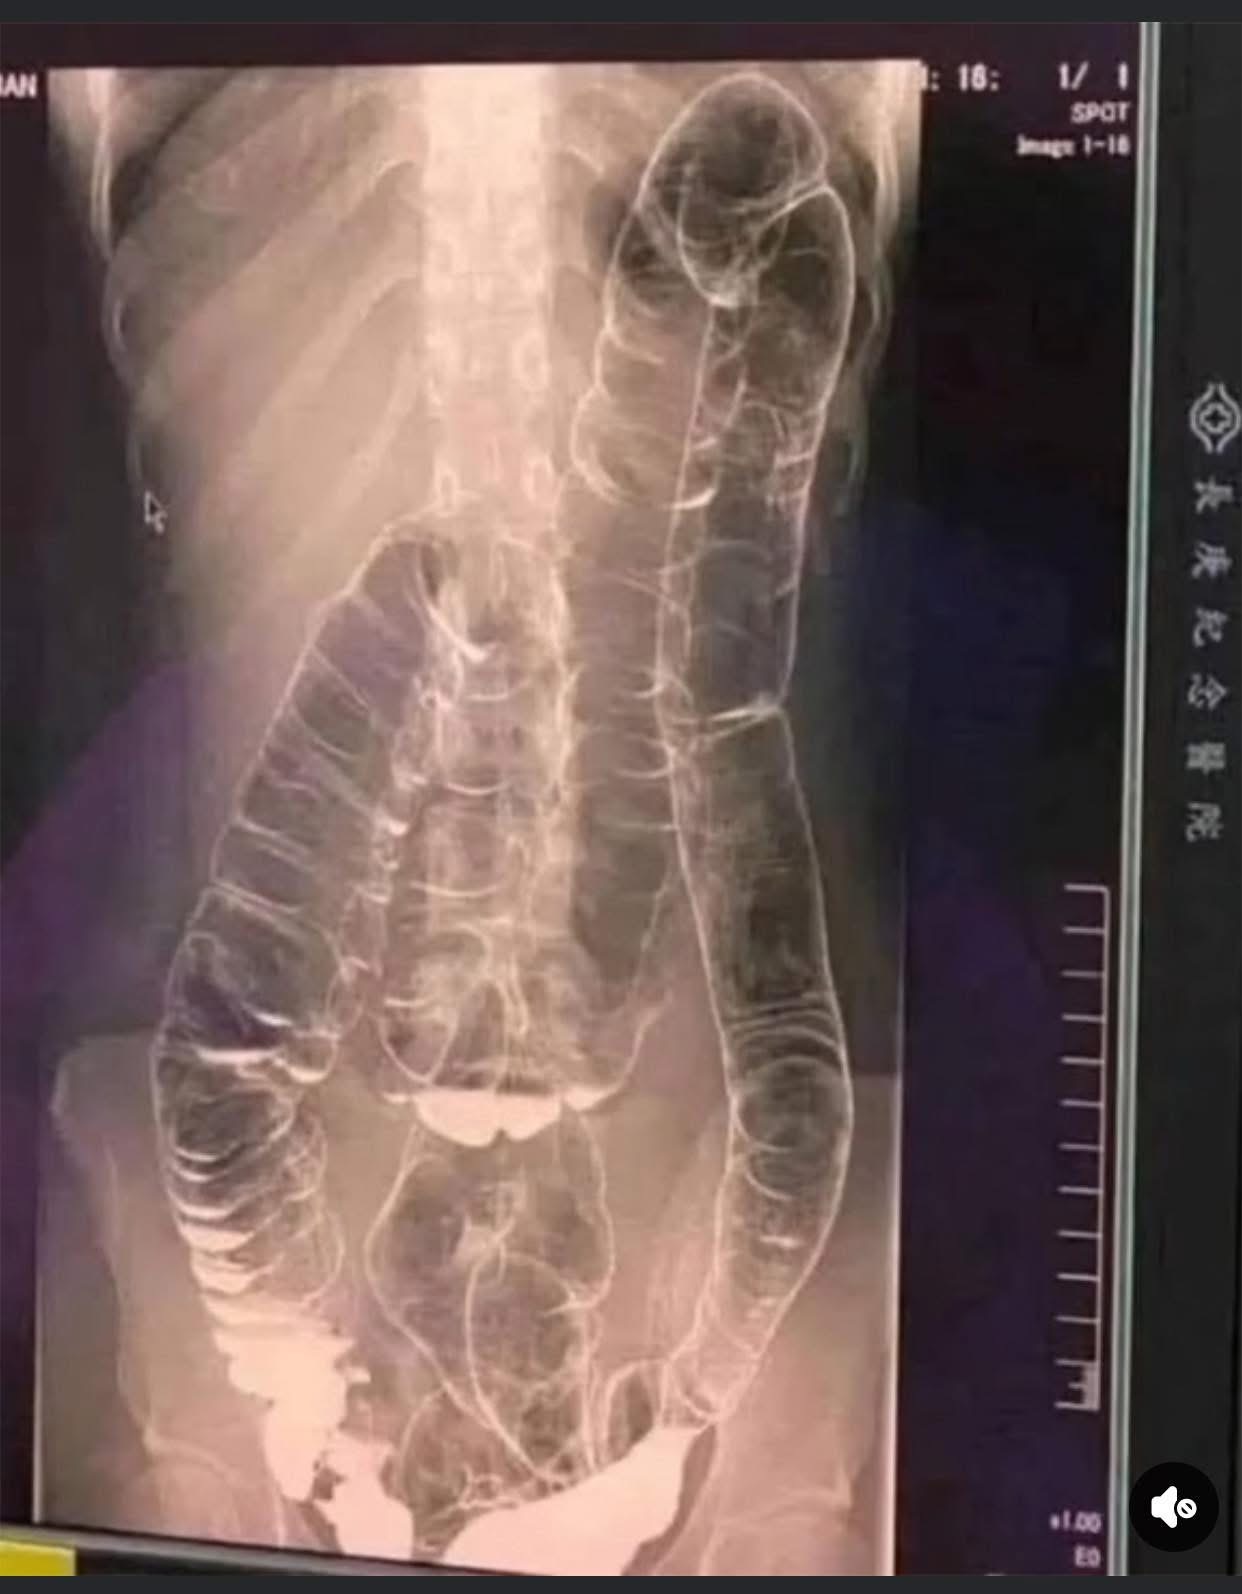

When waste accumulates in the colon due to an inefficient digestive system, it causes severe discomfort and bloating. Over time, the colon expands beyond its normal size, struggling to contain the excessive buildup of feces. In this case, medical imaging revealed a severely distended colon that had enlarged so much it reached up toward the chest, dangerously close to the heart. The stretching had nearly erased the colon’s natural folds and wrinkles, essential for its proper function. Left untreated, this condition could have led to life-threatening complications.